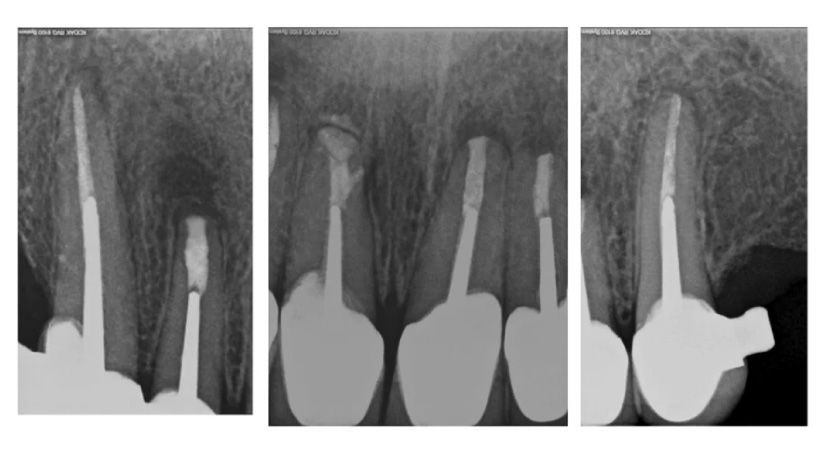

Se evaluaron radiografías digitales de pacientes que recibieron tratamiento endodóntico en una clínica odontológica universitaria alemana entre enero de 2011 y diciembre de 2020. Se incluyeron pacientes con lesiones periapicales visibles radiográficamente, una radiografía de control obtenida entre 6 y 12 meses después del tratamiento y un diagnóstico documentado de osteoporosis.

Se analizaron los cambios en el tamaño de la lesión periapical y las puntuaciones del Índice Periapical (PAI), comparándolos con una cohorte control emparejada por edad y grupo dental. Debido al tamaño limitado de la muestra, los análisis se consideraron exploratorios.

De 103,385 pacientes evaluados, 13 pacientes con osteoporosis (4 hombres, 9 mujeres) cumplieron todos los criterios de inclusión y fueron emparejados con 13 controles sanos. Ambos grupos mostraron una reducción en el tamaño de la lesión periapical con el tiempo (cambio medio: −2.47 mm en el grupo con osteoporosis y −1.90 mm en los controles).

Se observó una mejoría promedio de un grado en el índice PAI en ambas cohortes. No se detectaron diferencias estadísticamente significativas entre los grupos.